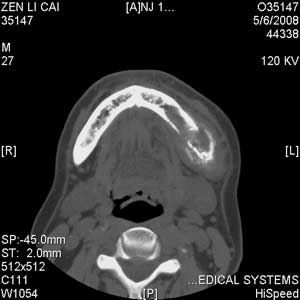

以下是引用jiangjing在2008-5-28 15:56:00的发言:[br]下颌骨左侧部骨质破坏,轻度膨胀,瘤骨形成,软组织肿胀考虑 恶性骨肿瘤-----肉瘤类